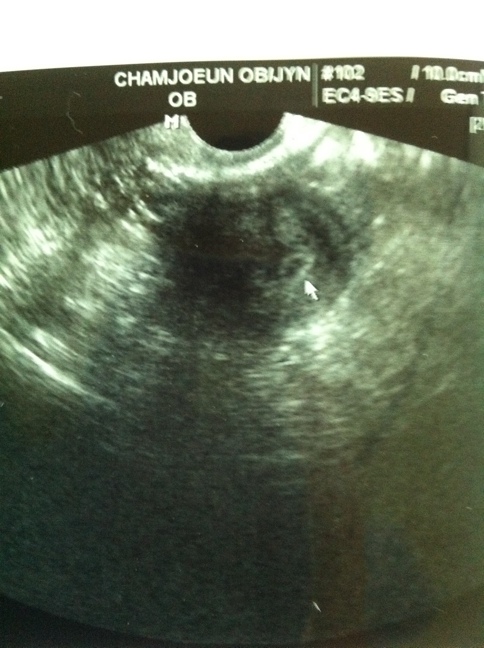

¿À´Ã°¬´Ù¿Ô¾î¿ä ¤¾ °ÅÀǸ·»ý±âÁØÀº4-5ÁÖÁ¤µ·µ¥ º´¿ø°¡´Ï ¾Ö±âÁýÅ©±âº¸°ï 3ÁÖÁ¤µµµÈ°Å·¡¿© ¤Ð¤ÐÂø»óÀ̴ʰԵƳª¹Ù¿© ¤Ð Á¦°¡µð´Ï´Â º´¿ø¿øÀå»ùÀº ¸»·Î °ÌÀ»³Ê¹« Áּſ© ¤Ð ÀڱÿÜÀÓ½ÅÀϰŶó°í ¿À´Ã°Ë»çÀü¿¡ ±×·¯´õ´Ï ¾Ö±âÁýº¸°í¼± ¾Ö±âÁýÀÌÀÌ´ë·Î ¾ÈŬ¼öµµÀÖ°í ¾Ö±âÁýÀºÅ©´Âµ¥ ¾È¿¡ ¾Ö±â°¡ ¾ø´Â°æ¿ì°¡ Á¾Á¾ÀÖ´Ù°í ¤Ð¤ÐÀ¸¾û ºÎµð ¿ì¸®Æ°Æ°ÀÌ °Ç°ÇÏ°Ô ÀÚ¶ö¼öÀÖµµ·Ï ¸¹Àº ÀÀ¿øºÎʵ右´Ï´Ù